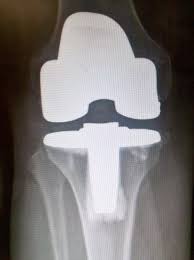

![]() |

Tirée de: Rev. bras. ortop. vol.46 no.4 São Paulo 2011 |